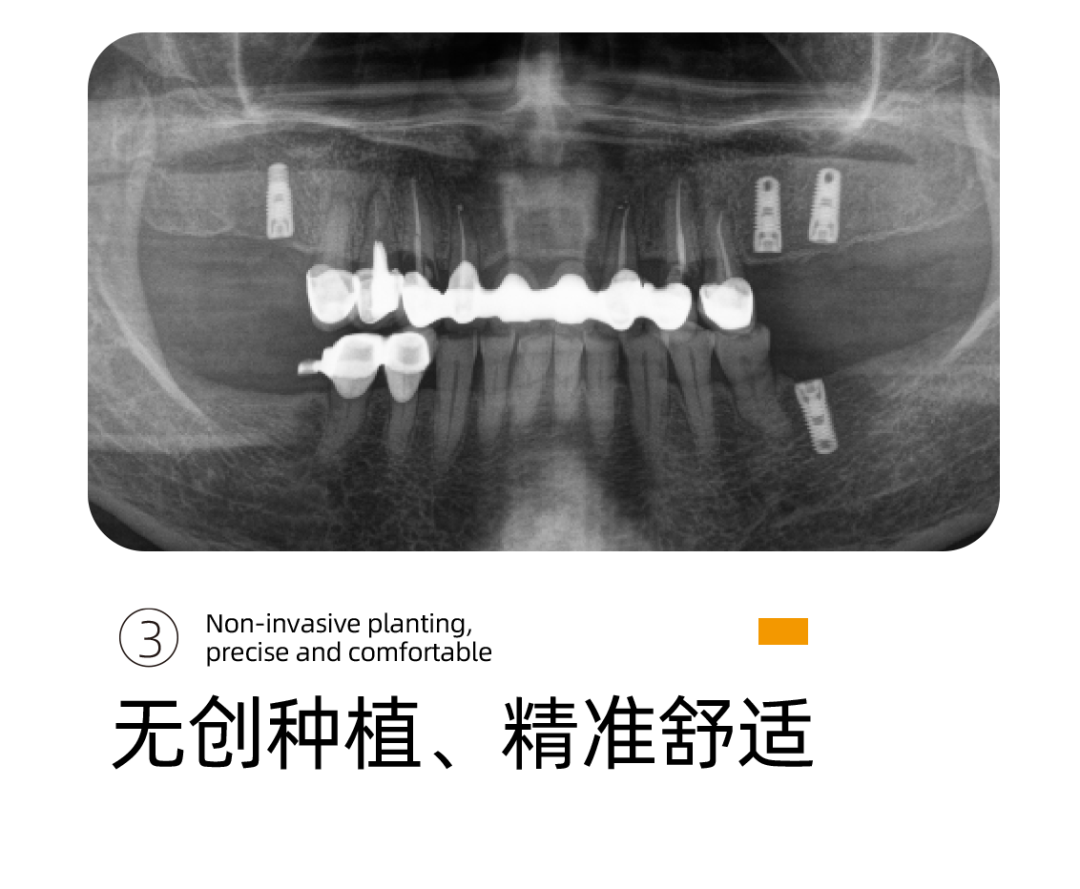

其实就是借助Sirona CBCT全景影像信息和相关修复信息为基础,借助数字化专业种植设计软件进行术前诊断和种植方案规划。

UNIC种植体系完美打造专属于患者的“私人订制”完整种植闭环,数字化微创种植结合数字化椅旁修复方式,真正实现当天种植、当天戴牙,其中最大的优点就是可以在术中减少患者的痛苦,提高患者的舒适感。

李雪松院长通过德国数字化口腔扫描设备获取的口内数据完全拟合设计,告别传统种植手术中通过大翻瓣暴露手术区域以及解剖结构的方式,缩短就诊以及手术时间,大幅度降低患者术中的疼痛感。

通过数字化种植手术导向模板,将术前制订的种植方案准确应用于种植手术和即刻修复的全过程,实现以修复为导向的牙种植修复。

它的优势在于种植医生借助数字化设备可以真正实现以修复为导向的种植理念,并且实际运用到临床操作中,实现微创种植,不翻瓣,将创口降到最低。

全数字化导板设计会依靠自身数字化的精确定位和微创特点,大大减少失误操作,提高种植手术的精准度。

精准、高效、微创性瞬间提升,伤口更小,出血更少,恢复的更快更好。